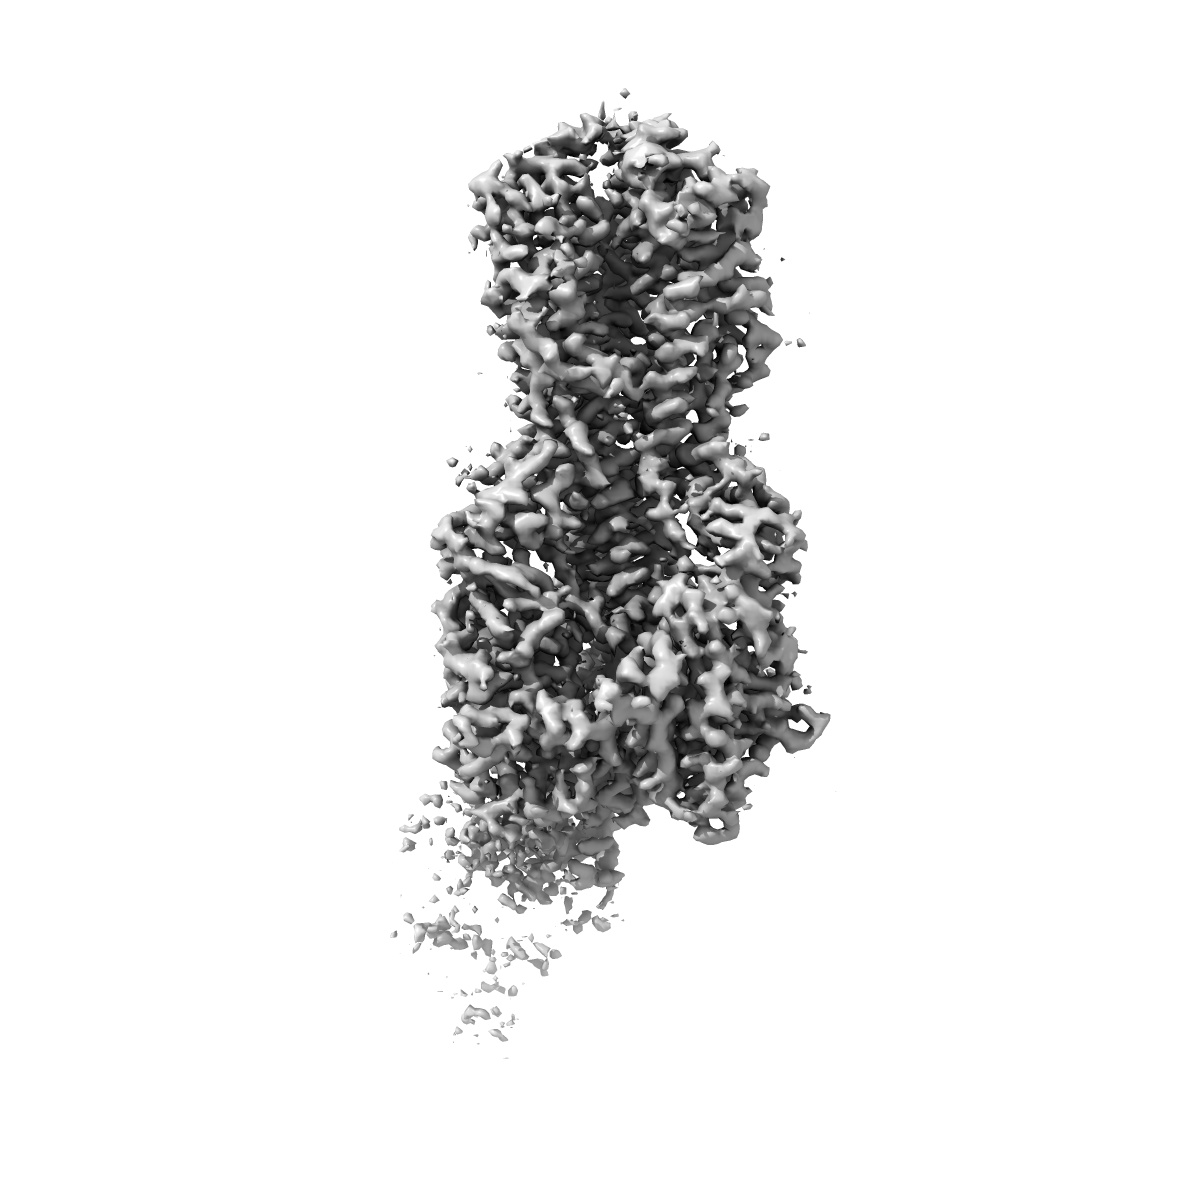

EMD-41472

H2 hemagglutinin (A/Singapore/1/1957) in complex with polyclonal Fab, pAb_1

Single-particle2.9 Å

Sample: H2 hemagglutinin (A/Singapore/1/1957) in complex with polyclonal Fab, pAb_1